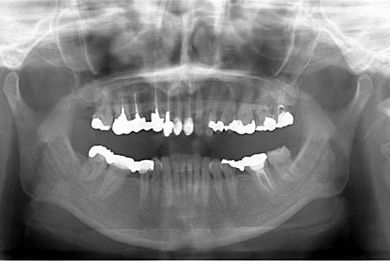

| 性別/年齢 | 女性 / 41歳 | ||||||||||||||||||||||||||||||||

| 主訴 | 歯が欠けたので、セラミック治療をお願いしたい。 | ||||||||||||||||||||||||||||||||

| 治療方針 | セラミック治療にて、審美的回復を行う。 | ||||||||||||||||||||||||||||||||

| 治療内容 | エンプレスオールセラミッククラウン4本(オールセラミック用土台4本) | ||||||||||||||||||||||||||||||||

| 総治療費 | 408,000円 | ||||||||||||||||||||||||||||||||

| 治療期間 | 4ヶ月 |